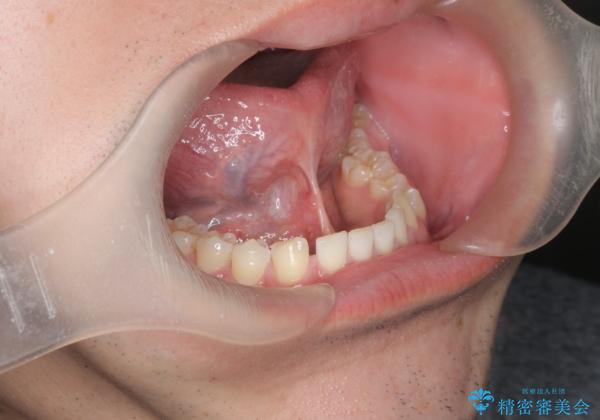

[ 舌小帯の形成術 ]ベロの動きを改善したい

- 舌の動きが幼少時より悪く、改善したいと来院されました。

舌の下部の小帯(ヒダ)の付着が長く、舌の動きを制限している状態を、形成術(小手術)により改善します。

小帯の形成術は約10分程度で終了し、1週間後に抜糸を行い終了となります。